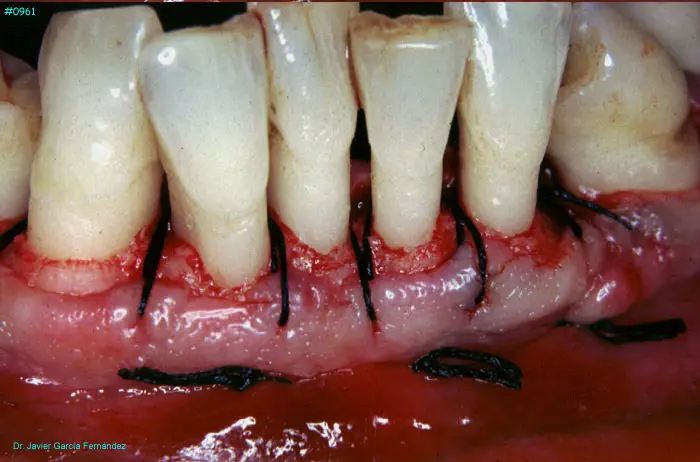

Atlas of Surgical Techniques in Periodontics. Chapter III. Atlas de Técnicas Quirúrgicas en Periodoncia